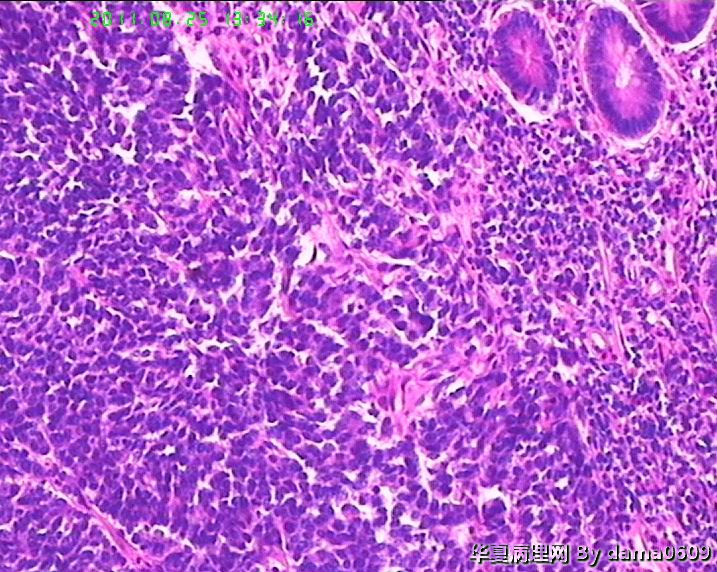

患者男性,39岁。以回盲部肿物行肠镜检查、活检。镜下四块组织内有两块见呈巢状的小细胞(如图

),另两块为粘膜慢性炎表现及坏死组织。学生不知如何分类:未分化癌?类癌?小细胞癌?请老师指教。谢谢!

细胞核较小、深染、一致,核分裂象少见,支持典型类癌。

神经内分泌肿瘤 淋巴瘤 低分化腺癌。。。

神经内分泌肿瘤

又仔细看了一下片子,有核仁,见到核分裂,是否可以定“未分化腺癌”呢?

楼主是想说“未分化癌”?片子切的比较厚,考虑神经内分泌肿瘤,低分化腺癌待排。

神经内分泌肿瘤?低分化腺癌?标一下神经内分泌标记

高级别癌,活检标本,可做IHC先排除高级别神经内分泌肿瘤。

如果神经内分泌阴性,明确分型等手术根治标本。